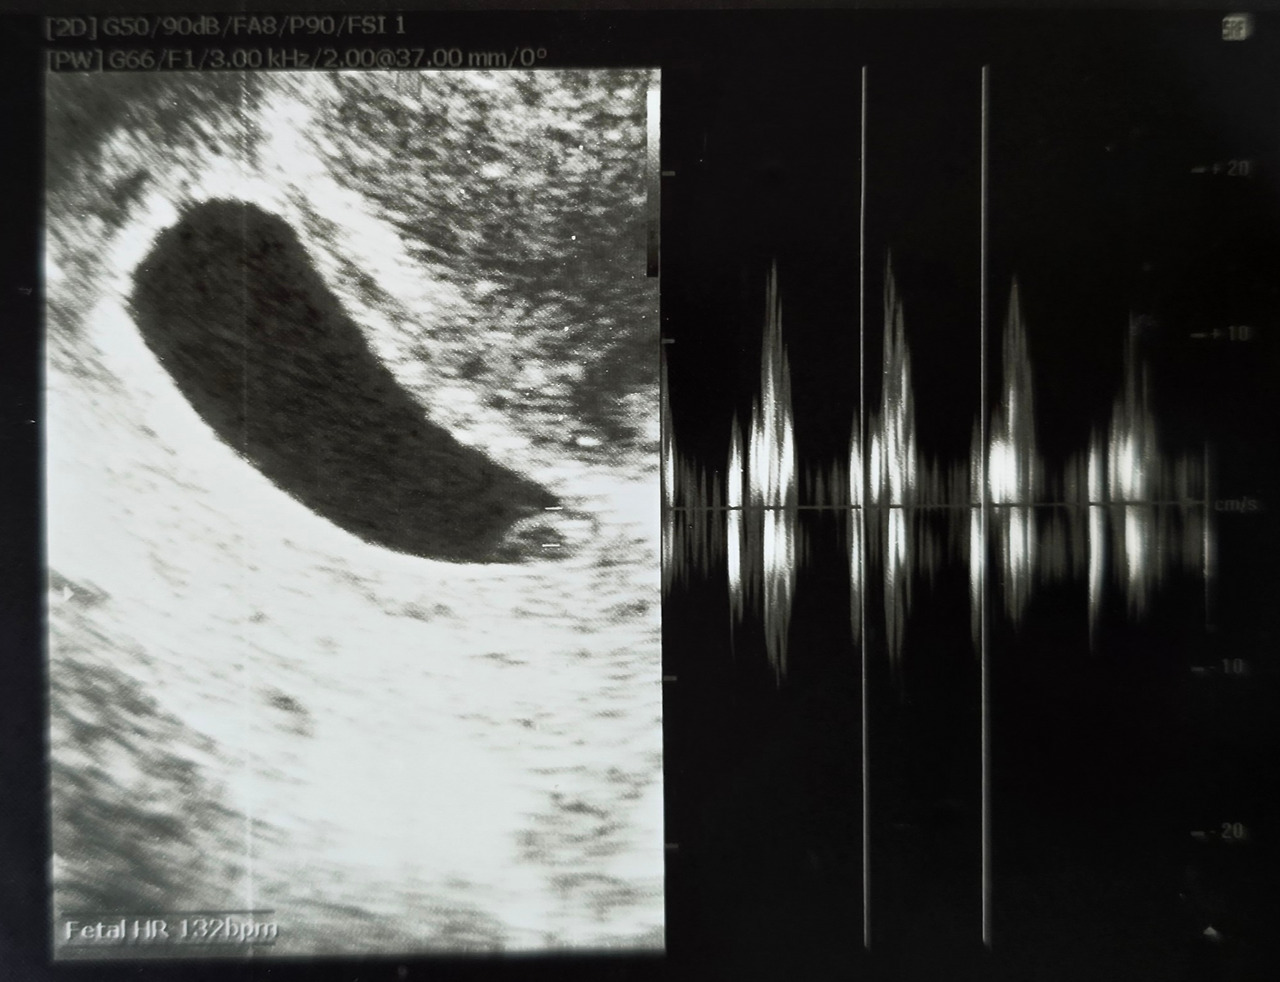

“둥둥둥둥”

1분에 132번. 처음 들은 둥글이의 심장은 시간이 부족하다는 듯 빠르게 뛰고 있었다. 6mm밖에 되지 않는 몸에서 어떻게 그렇게 힘이 넘치는지 심장소리는 세상을 채울 듯 맥동했다.

지금 생각해 보면 의사 선생님이 스피커 볼륨을 많이 키워 놓았던 것 같긴 하지만 그때는 가슴까지 울리는 고동 소리가 너무 감격스러워 그런 생각을 할 겨를 따위는 없었다.